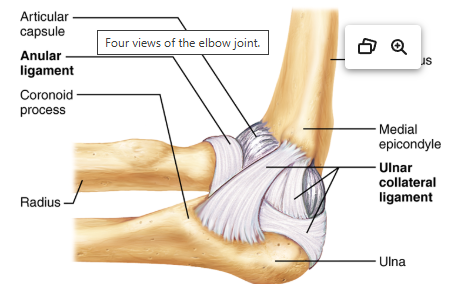

What is the humeroradial/humeroulnar joint?

The elbow joint.

What is the joint shown here? (Be specific, list both names).

The humeroradial/humeroulnar joint.

Find the radial collateral ligament.

(See bolded text in image).

Find the ulnar collateral ligament.

(See bolded text in image).

What is the name of the superior and anterior (top-right) ligament?

Annular ligament.